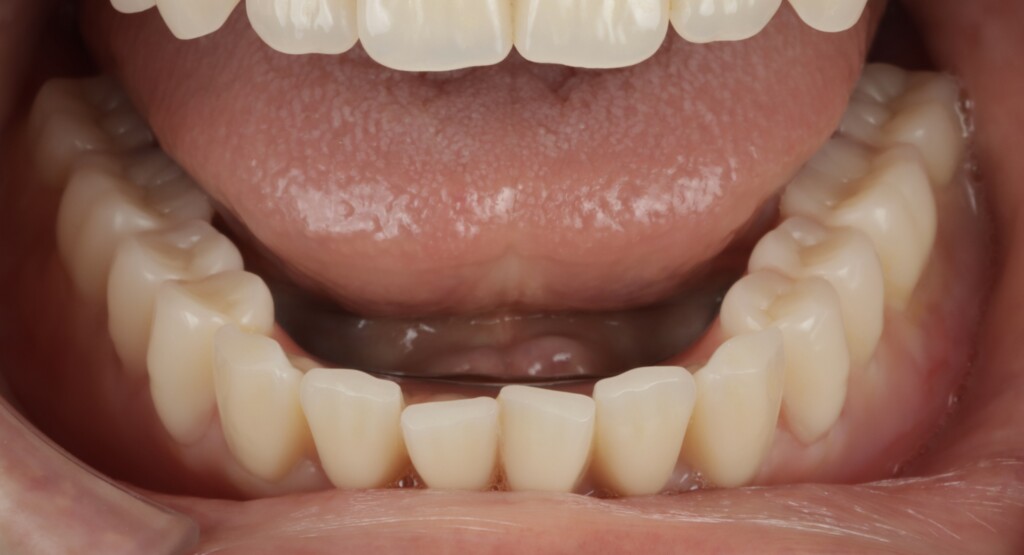

写真3:下顎の歯ぐきの状態

下顎は無歯顎の状態で、歯ぐきの痩せも認められたため、入れ歯の安定が得にくい条件でした。しかし上顎と同様に、精密義歯を製作することで、適合性と安定性の向上を図りました。

歯ぐきは歯や骨のような硬い組織ではなく、力が加わるとおよそ2mm程度沈み込みます。そのため、入れ歯は前後・左右に傾きやすくなり、外れやすさや噛みにくさの原因となります。

精密な入れ歯を製作するうえでは、この「歯ぐきの沈み込み(粘膜被圧)」を考慮し、実際に噛んだときに近い状態を再現することが重要です。そこで今回は、機能時に近い被圧状態を再現するために「閉口機能印象」を行いました。口を閉じて噛む力が加わった状態で型取りを行うことで、使用時に近い粘膜の状態を反映でき、結果として外れにくく安定した入れ歯の製作につながります。